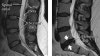

- MRI에서 디스크(disc)에 퇴행성 변화(degeneration)나 추간판탈출(herniation disc)이 보일 때

MRI에서 디스크에 퇴행성 변화를 보인다는 이유로 디스크 진단을 받는 환자분들이 많이 있습니다.

하지만 이것 역시 부적절한 진단이 될 가능성이 아주 많습니다.

허리 통증이 없는 중년 이상의 성인을 대상으로 MRI를 찍게 되면 대부분 디스크에서 퇴행성 변화를 볼 수 있습니다.

따라서 중년 이상의 성인에서 디스크에 퇴행성 변화를 보인다고 해서 디스크 진단을 내려서는 곤란합니다.

퇴행성 변화가 아닌 일정 정도의 추간판탈출(herniation)이 있는 경우에도 마찬가지입니다.

노화의 과정으로써 자연스럽게 진행된 추간판탈출은 임상 증상을 일으키지 않습니다.

따라서 MRI는 디스크 증상을 보였던 환자에서 진단을 검증하는 방법으로 사용될 수 있으나 MRI 소견만으로 디스크를 진단하기에는 무리가 따릅니다.